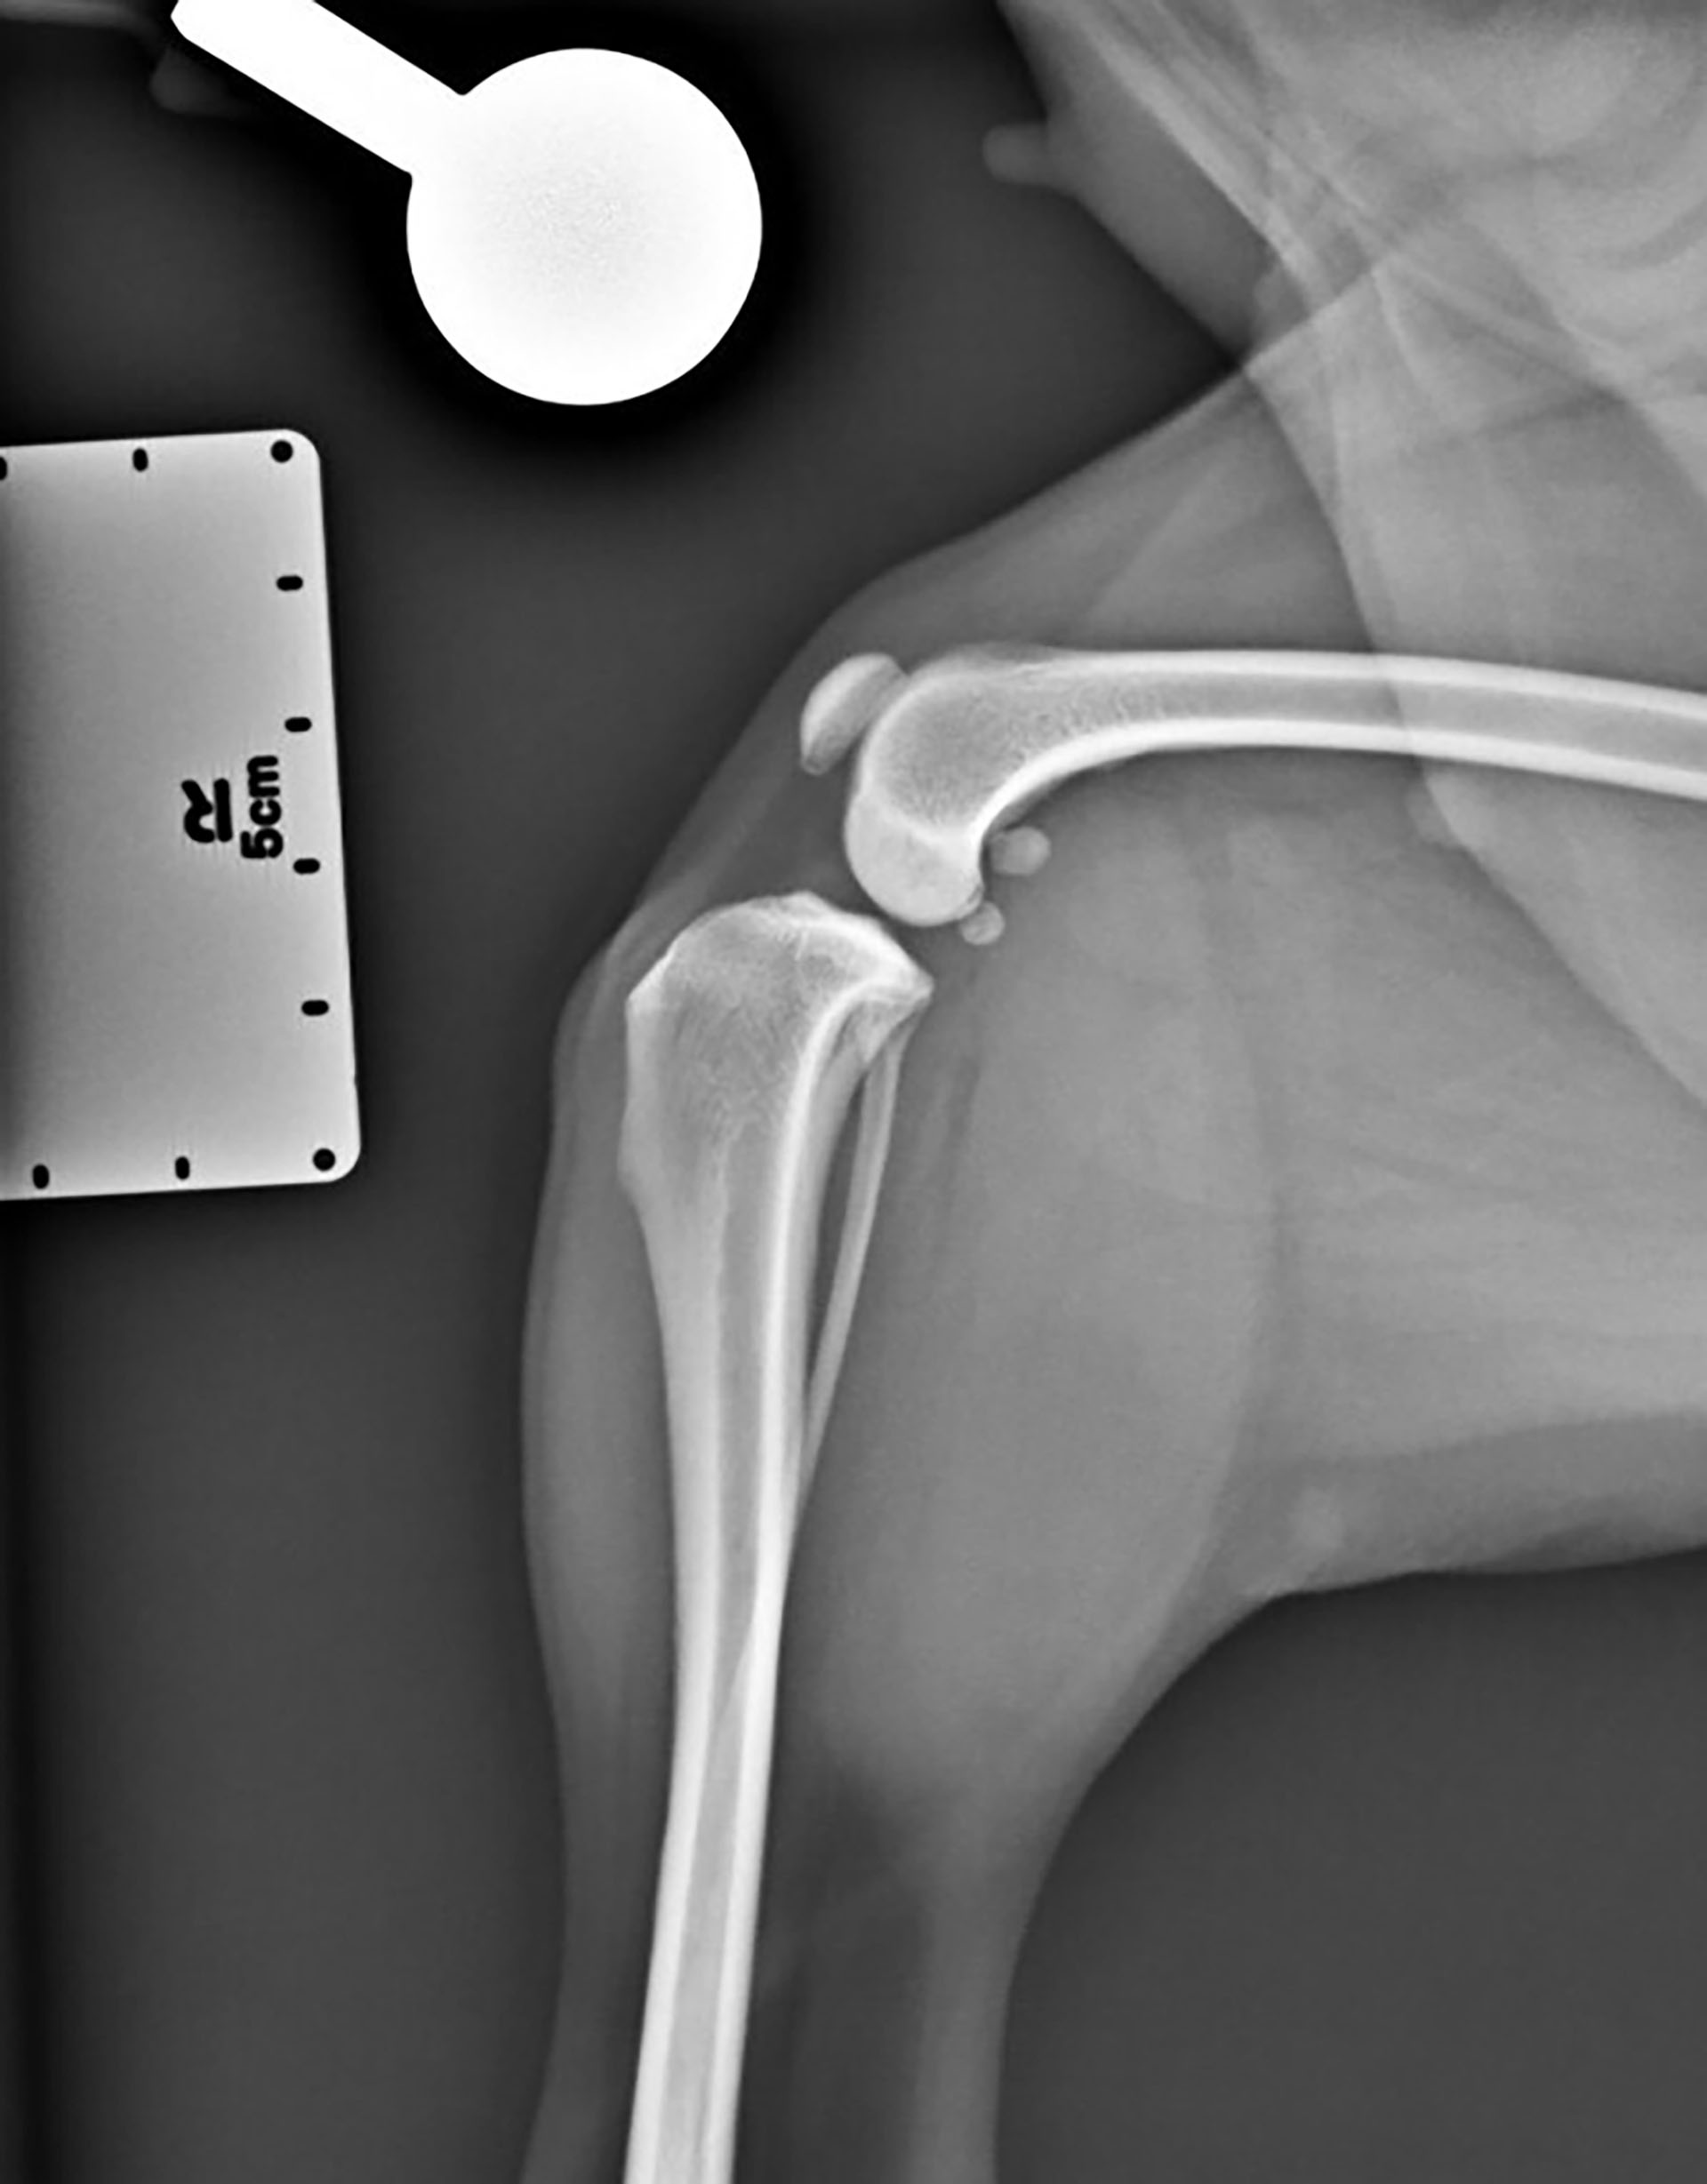

Figur 2. Laterolateral projeksjon av høyre kneledd uten tegn til effusjon.